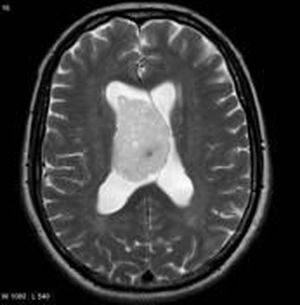

What is it

Please diagnosis

Acute bleeding ?

Epandimoma